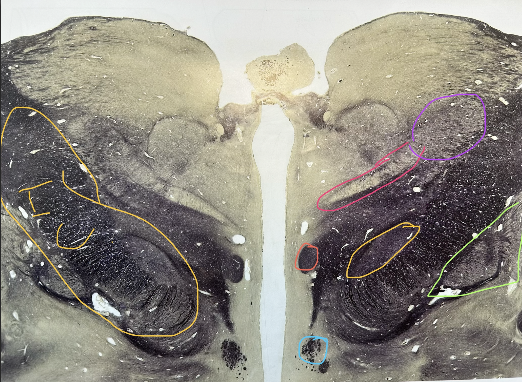

whats in yellow

subthalamic nucleus

whats in green

globus pallidus, internal and external

whats in salmon

mammilothalamic tract

whats in pink

ventral posteromedial nucleus of thalamus

whats in purple

ventral posterolateral nucleus of thalamus

whats in blue

column of fornix